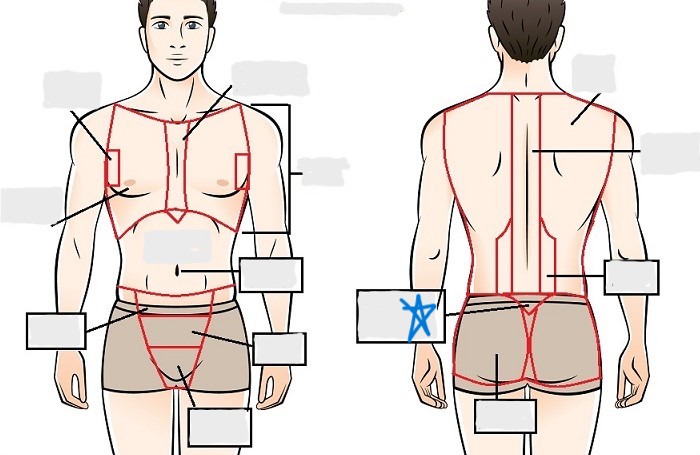

axial

cephalic

occipital

frontal

otic

orbital

nasal

oral

mental

cervical

dorsal

scapular

vertebral

lumbar

sacral

gluteal

thoracic

sternal

mammary

axillary

abdominal

umbilical

pelvic

inguinal

pubic

perineal

appendicular

acromial

brachial

antecubital

olecranal

antebrachial

carpal

manus

coxal

femoral

patellar

popliteal

crural

sural

peroneal

calcaneal

plantar